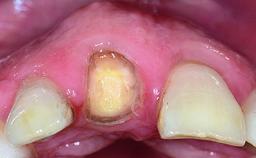

In 2008, a healthy 15-year-old female, non-smoking patient presented at our clinic with a major esthetic problem of tooth 21. Her dental history revealed that the tooth had been avulsed by trauma years before. As a result, the replanted and temporarily splinted tooth had ankylosed and was in severe apical malposition. The ankylosed tooth exhibited a significant gingival recession that disturbed the patient greatly. Due to the patient’s low age and with her skeletal growth not completed, periodic follow-up visits were scheduled to monitor the situation until the patient was old enough for implant therapy.